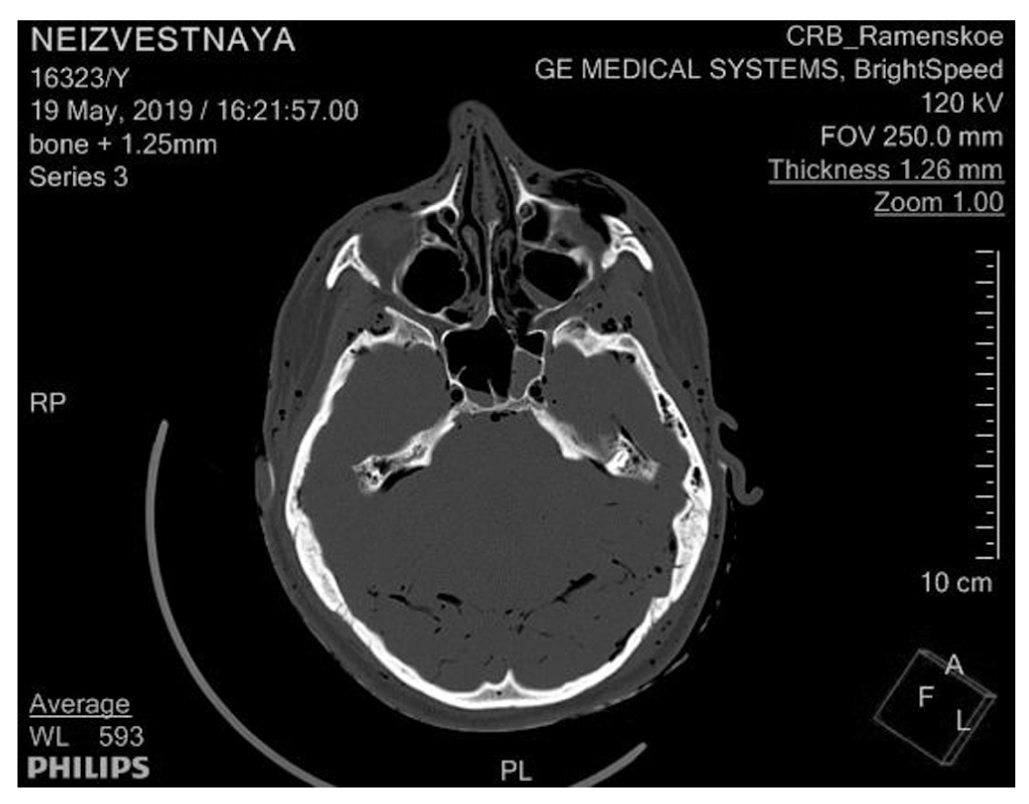

При компьютерной томографии трупа врачом-рентгенологом установлено: в обеих верхнечелюстных, основной и лобной пазухах, в отдельных клетках решетчатого лабиринта с обеих сторон определяется содержимое с горизонтальным уровнем жидкости, с наибольшим объемом жидкости в левой половине лобной пазухи (рис. 3, 4).

Рис. 3. Жидкость в лобной пазухе

Рис. 4. Жидкость в пазухах